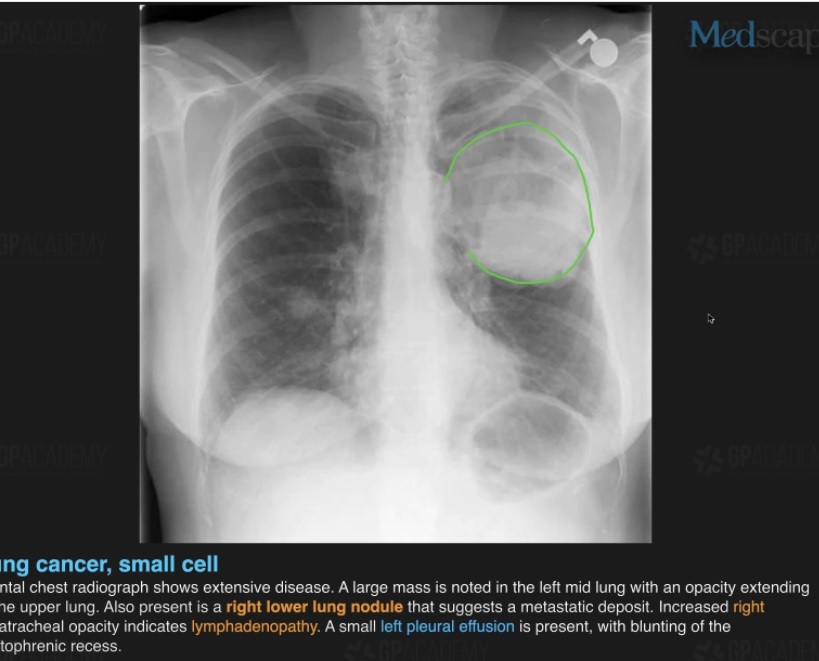

?Type of lung cancer

-Central airways

-Smokers

-Rapid doubling time

A

Small cell lung cancer